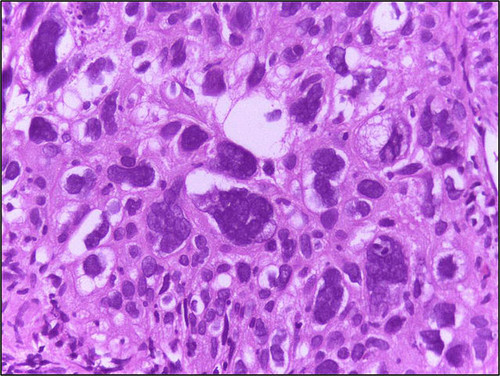

Das unkontrollierte Wachstum von Krebszellen versuchen Forscher seit Jahren zu verstehen und in den Griff zu bekommen. Jetzt haben Wissenschaftler der Mayo Clinic in Florida und der Universität Genf offensichtlich die fehlende „Wachstumsbremse“ entdeckt. Laut ihrem jetzt in der Fachzeitschrift „Nature Cell Biology“ veröffentlichten Studienbericht, ist es gelungen, menschliche Tumorzellen umzuprogrammieren und das Wuchern zu stoppen.

Sie fanden heraus, dass bei der Steuerung der Funktionen der Adhäsionsproteine und bestimmter Microprozessoren (miRNAs) ein bestimmtes Protein wichtig ist. Ohne dieses Protein (PLEKHA7) wissen die Zellen nicht, wann sie aufhören sollen sich zu teilen. Nachdem die Forscher den PLEKHA7-Level durch Injektion korrigiert hatten, hörten die Tumorzellen auf zu wachsen und erholten sich. Dr. Anastasiadis, Vorsitzende der Abteilung für Krebsbiologie an der Mayo Clinic Florida, schreibt in seinem Bericht, dass bereits erste Studien mit ziemlich aggressiven Krebszellen positiv verlaufen seien.

Die Wissenschaftler suchen jetzt nach einer effizienten Lösung für die Re-Programmierung der fehlgesteuerten miRNA. Das bisherige Ergebnis ist sicherlich ein großer Schritt für die Krebstherapie. Doch Krebsforscher warnen vor zu großer Euphorie, denn der Weg vom Labor bis zum Krebspatient sei noch lang und ein Erfolg noch nicht garantiert.